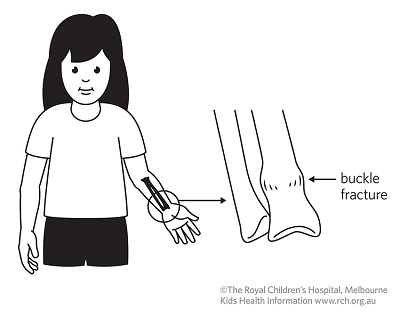

There is rarely any problem with healing and the children can do all the things they did before. Your hand therapist at Action Rehab will be able. John just needed a cast.īuckle fractures usually heal very quickly and very nicely. More-severe greenstick fractures may cause an obvious deformity, accompanied by significant pain and swelling. If it does need to be straightened, it can be a bit difficult, due to the strong periosteum. What is a buckle fracture Your child has suffered a ‘buckle’ fracture of their arm and wrist. If a buckle fracture of the radius has only a little bend (depending on age, 10 to 20 degrees), it does not need to be reduced (bent back straight).

This is usually not torn and holds the bones in place. In addition, the layer of soft tissue over the bone, called the periosteum (which means the "tissue around the bone"), is quite thick and strong. When the bones of a child are stressed more than they can tolerate, they can buckle (which means bend) or deform like a green stick. The bones of children are still growing and are not as brittle as the bones of adults. This fracture is called a buckle fracture or a greenstick fracture. The large bone on the left is called the radius, the other bone is called the ulna. This is a close-up view of the wrist area. There is only a small bending of the cortex (outer part) of the bone. Surgical repair of pediatric hand and wrist fractures is rarely required in situations where the bone cannot be set straight or if it not healing properly with cast treatment.The fracture is indicated by the red arrows. Sometime the fracture will need to be “set” straight before splinting. Delayed treatment of pediatric fractures can lead to undesirable outcomes including malunion (bone doesn’t heal straight), and nonunion (bone doesn’t heal at all).Īnd casting are the mainstays of nonoperative treatment for fractures that are stable and not badly displaced (out of alignment). Even without these warning signs, it is best to seek urgent treatment so that the fracture can be set straight and Or “tight” swelling, significant deformity, or any open wounds around the hand or wrist (possible open or compound fracture). Suspected hand and wrist fractures warrant emergent treatment if your child is experiencing hand numbness and tingling, severe Yes! Some fractures are obvious if there is a deformity, but typically X-ray is used to definitively diagnose the fracture and plan treatment. Is There a Test for Hand and Wrist Fractures?

Cover it with a towel before you place it on your skin. Use an ice pack, or put crushed ice in a plastic bag. Finger hyperextension / jamming injuries Apply ice on your wrist for 15 to 20 minutes every hour or as directed.Direct blows to the hand or wrist (sports, vehicle accidents).Fall onto an outstretched hand (most common).Most hand and wrist fractures in children are caused by injuries: The fractures occur around the soft growth plates at the wrist and bases of the fingers. Because children’s bones are more flexible than adults’, sometimes they “bend” or “buckle” like a “green stick” rather than cracking. These are all just different ways of describing a fracture. You’ve been told the bone was “broken”, “hairline”, “green stick”, “buckled”, “cracked”, “chipped”, “split”, “shattered”, or “splintered”, Fractures are simply breaks or cracks in the bone. Unfortunately, fractures are a right-of-passage for most children. Of all ages, and when they land on their outstretched hand or wrist, injuries can occur. Kids are active, but not always graceful! Falls happen to children What Are Pediatric Hand and Wrist Fractures?